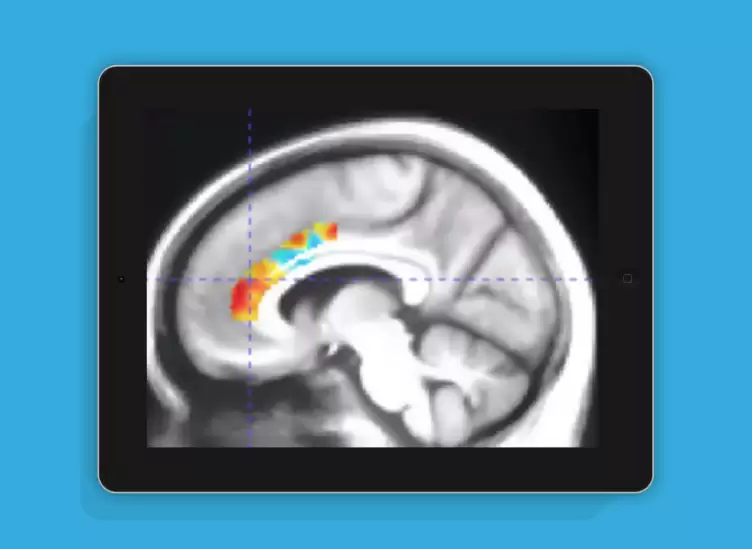

这项研究由Mouna Attarha领衔的团队完成,重点关注计算机化认知训练对健康老年群体脑神经功能的影响。通过使用[18F]Fluoroethoxybenzovesamicol正电子发射断层扫描技术,研究人员观察了参与者大脑中囊泡乙酰胆碱转运蛋白水平的变化,旨在评估认知训练对神经可塑性的促进作用。研究采用随机对照临床试验的形式展开,项目名称为"通过神经可塑性基础计算机化训练改善老年神经系统健康"(INHANCE),相关成果已正式发表。

研究共招募了92名平均年龄71.9岁的健康老年人,这些参与者平均接受过16.5年的教育。在为期十周的干预过程中,他们定期完成了专门设计的认知训练游戏任务。结果显示,经过系统训练后,参与者在多项认知功能指标上均表现出明显提升,整体效果相当于将大脑的衰老进程推迟了约十年。